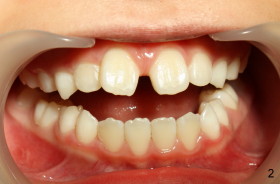

Eight-year-two-month girl has diastema between the maxillary central incisors.  It appears that the upper labial frenum (Fig.3 arrowheads, mirror view) bisects the interdental papilla (Fig.5).  Frenectomy is planned before orthodontic closure of the diastema.  Fig.4 is pre-op X-ray. Five months later, the diastema is closed.  The frenum appears to recede upward (Fig.6).  The bisected papilla seems to fuse (Fig.6,7).  Although the diastema has tendency to relapse when power chains are not used, fixed lingual retainer is planned to prevent the relapse when brackets are to be removed.  It appears that frenectomy is not so highly necessary for this purpose.

The patient's mother wonders whether frenectomy can improve the short upper lip (Fig.1).  What is your opinion?